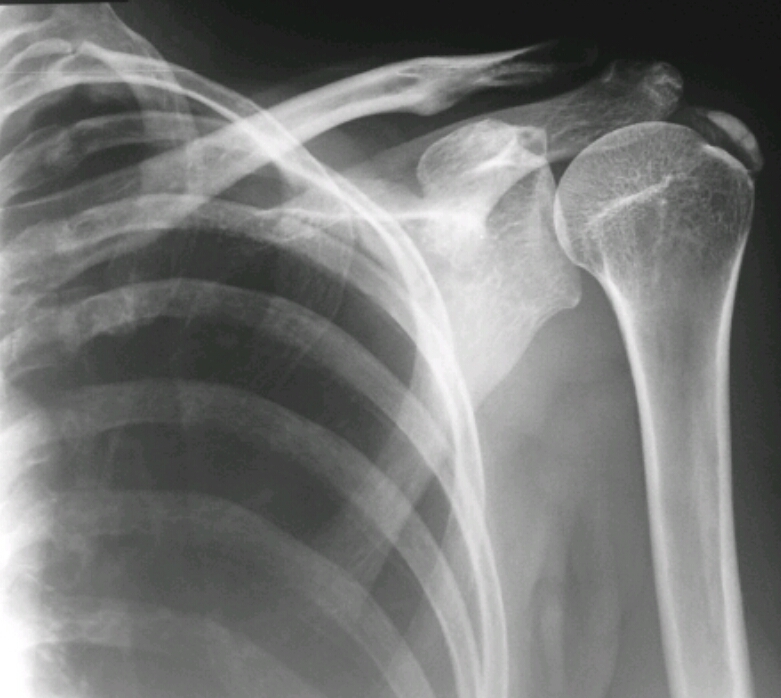

What disease is this? Name the changes that make you know that.

Elevation of humeral head

Degenerative enthesopathic changes of humeral head

Spurring of acromion process

Rotator cuff (supraspinatus) degeneration